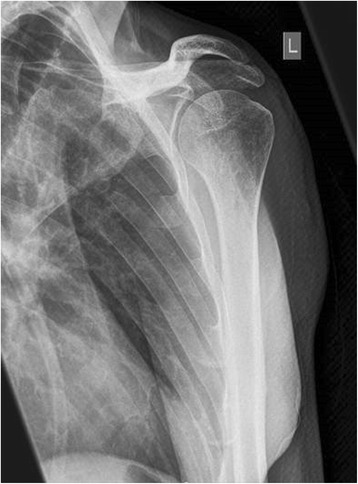

Figure 5.

X-ray of the upper arm shows a swelling of the soft-tissue in projection to the lower margin of the deltoid muscle (arrow).